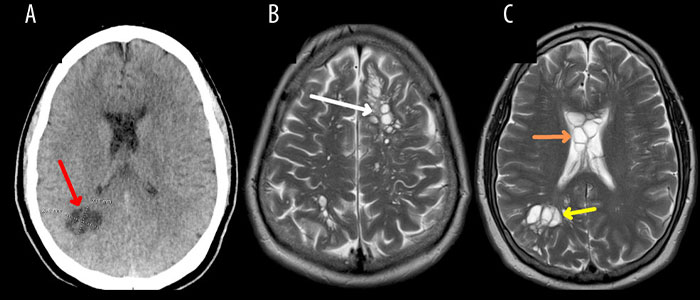

Image credits: amjcaserep.com